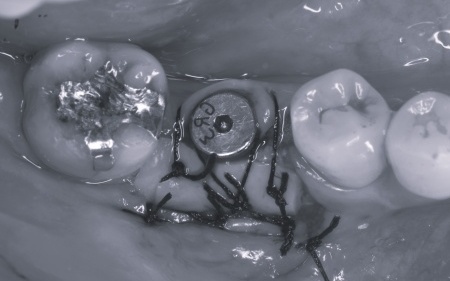

さらに虫歯が再発していた左上奥歯については、虫歯をしっかりと取り除いたうえで被せ物による修復治療を提案しました。 それぞれのメリット・デメリットを丁寧に説明したところ、治療計画に同意いただきました。 まず、歯周基本治療から開始しました。 下左右の第1大臼歯を抜歯し、その部位にインプラントを埋め込む手術を行いました。同時に、インプラントの隣にある下の第2大臼歯に対して歯周組織再生療法を施しています。 また、左上の奥歯は虫歯を取り除いたあと、歯の形を整えて型取りを行い、最終的にジルコニアクラウンを装着しています。 段階的に治療を進め、すべての治療を終了しました。 |

| 費用 | 約1,930,000円 【内訳】 歯周組織再生療法4ヶ所、インプラント2本、角化歯肉移植、ジルコニアクラウン |